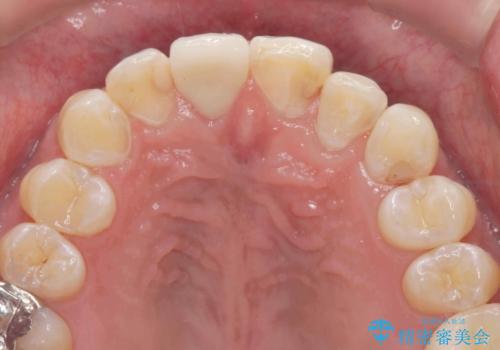

奥に位置している前歯を部分ワイヤー矯正ののちマウスピース矯正インビザラインで並べ、矯正治療後に審美的なジルコニアクラウンを作製していきます。

前歯の並びが改善し、色調の気になっていたクラウンの審美性も大きく改善することができました。